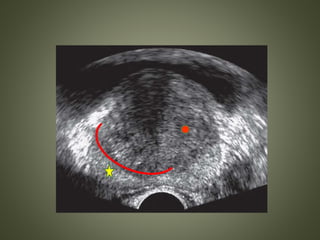

Typical hypoechoic peripheral zone lesion

Elastography of same lesion blue color in lesion, implying stiff tissue

ELASTOGRAPHY • Elastography createsa color-coded map of tissue stiffness. Prostate tumors Increased cell density Change of tissue elasticity and stiffness Detection by strain imaging

• Tumors tendto be stiffer than benign tissue. • False-positive results are seen with chronic inflammation and atrophy.

Typical hypoechoic peripheralzone lesion Elastography of same lesion blue color in lesion, implying stiff tissue